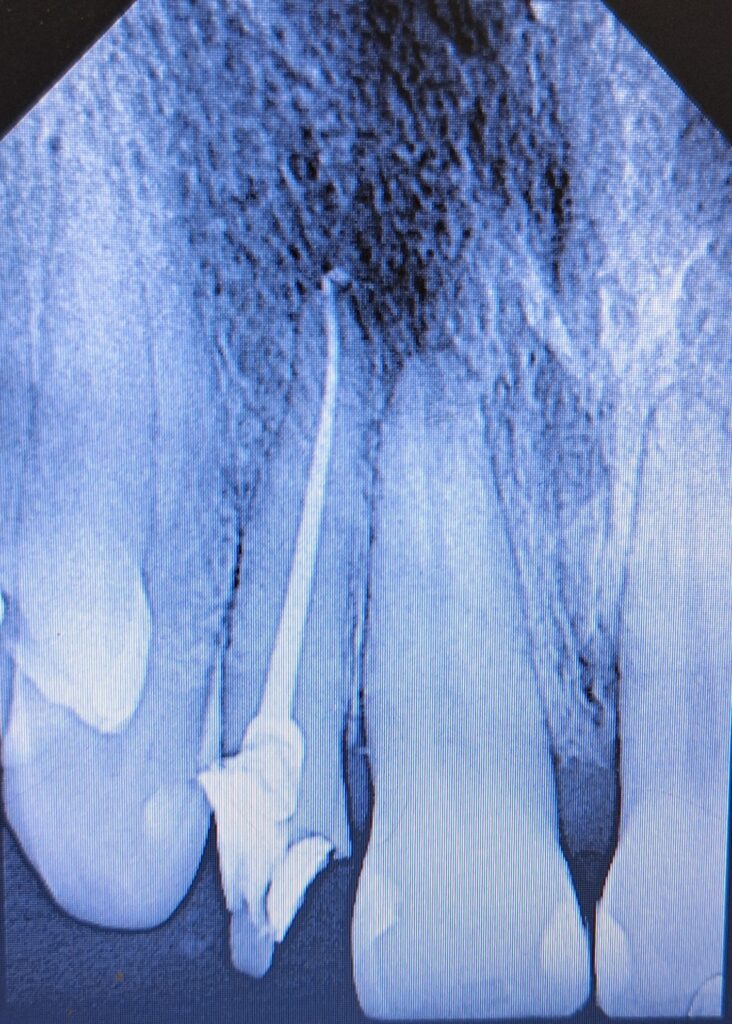

Veja alguns de meus casos